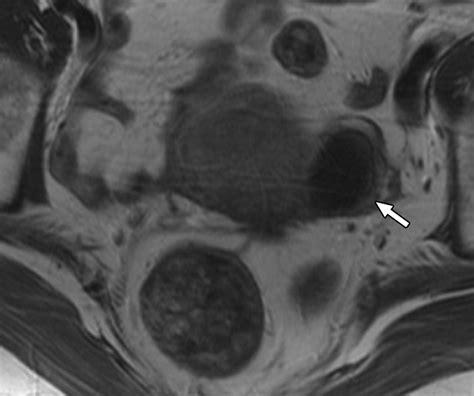

Radiologists look for "blooming effects" on the images, where small, dark spots represent paramagnetic substances like blood products. Because the signal decay is accelerated in regions with high iron or deoxyhemoglobin content, these areas appear as dark, high-contrast signals. Interpreting these images requires an understanding of how to differentiate between normal venous blood and pathological hemorrhages. For instance, the presence of blood in deep brain nuclei versus the cortex can indicate vastly different underlying etiologies, such as hypertensive vasculopathy or cerebral amyloid angiopathy.